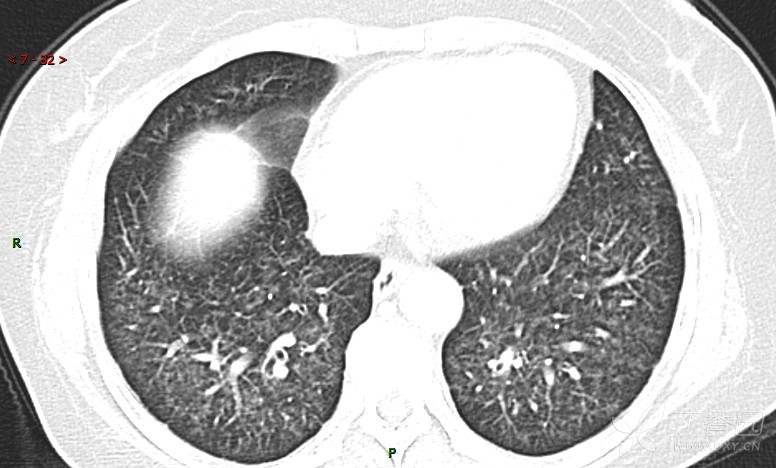

肺内弥漫性网状结节影,PET-CT却无阳性病灶,这是?(附其他2例链接)

糖类抗原15-3 70.7 U/ml ↑ 0--31.3

癌胚抗原 57.12 ng/mL ↑ 0--5

糖抗原125 166.8 U/ml ↑ 0--35

细胞角蛋白19片段测定 8.32 ng/ml ↑ ≤3.3

糖抗原199 901.79 U/ml ↑ 0--37

AFP、NSE(-)

患者活检肺组织后行PET/CT检查